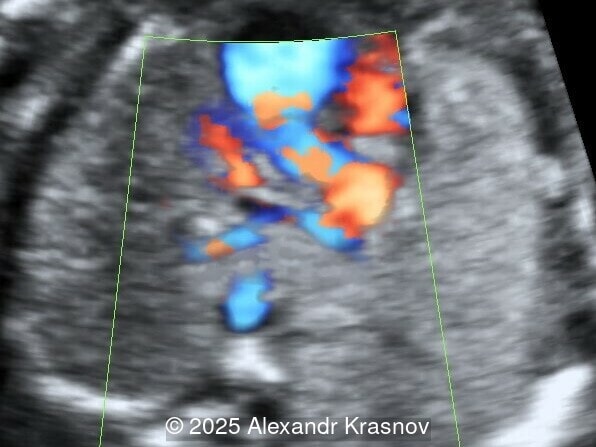

Image 2

Our ultrasound showed biometry data corresponding to 21 weeks of gestation. During echocardiography, an abnormal drainage of the pulmonary veins was detected in which the pulmonary veins drain into a venous collector linked to the superior vena cava. The four-chamber view and the three-vessel view were altered and raised suspicion of a pathology. The grayscale and color Doppler images of the four-chamber view indicate a smooth posterior wall of the left atrium, increased distance between the left atrium and the descending aorta and the absence of pulmonary veins entering the left atrium (Image 1, 2; Video 1, 2). In the three-vessel view, the diameter of the superior vena cava appears larger than that of the aorta (Image 3, Video 3). In the images of the venae cava, a significant difference is seen between the diameters of the inferior and superior vena cava with significant enlargement of the superior vena cava (Image 4, Video 4). Additionally, there is a pulmonary venous confluent chamber (“twig sign”) behind the left atrium (Image and Video 5). A vertical ascending vein connects the confluent chamber with the superior vena cava where it drains blood from the pulmonary veins (Images 6, 7; Video 6).